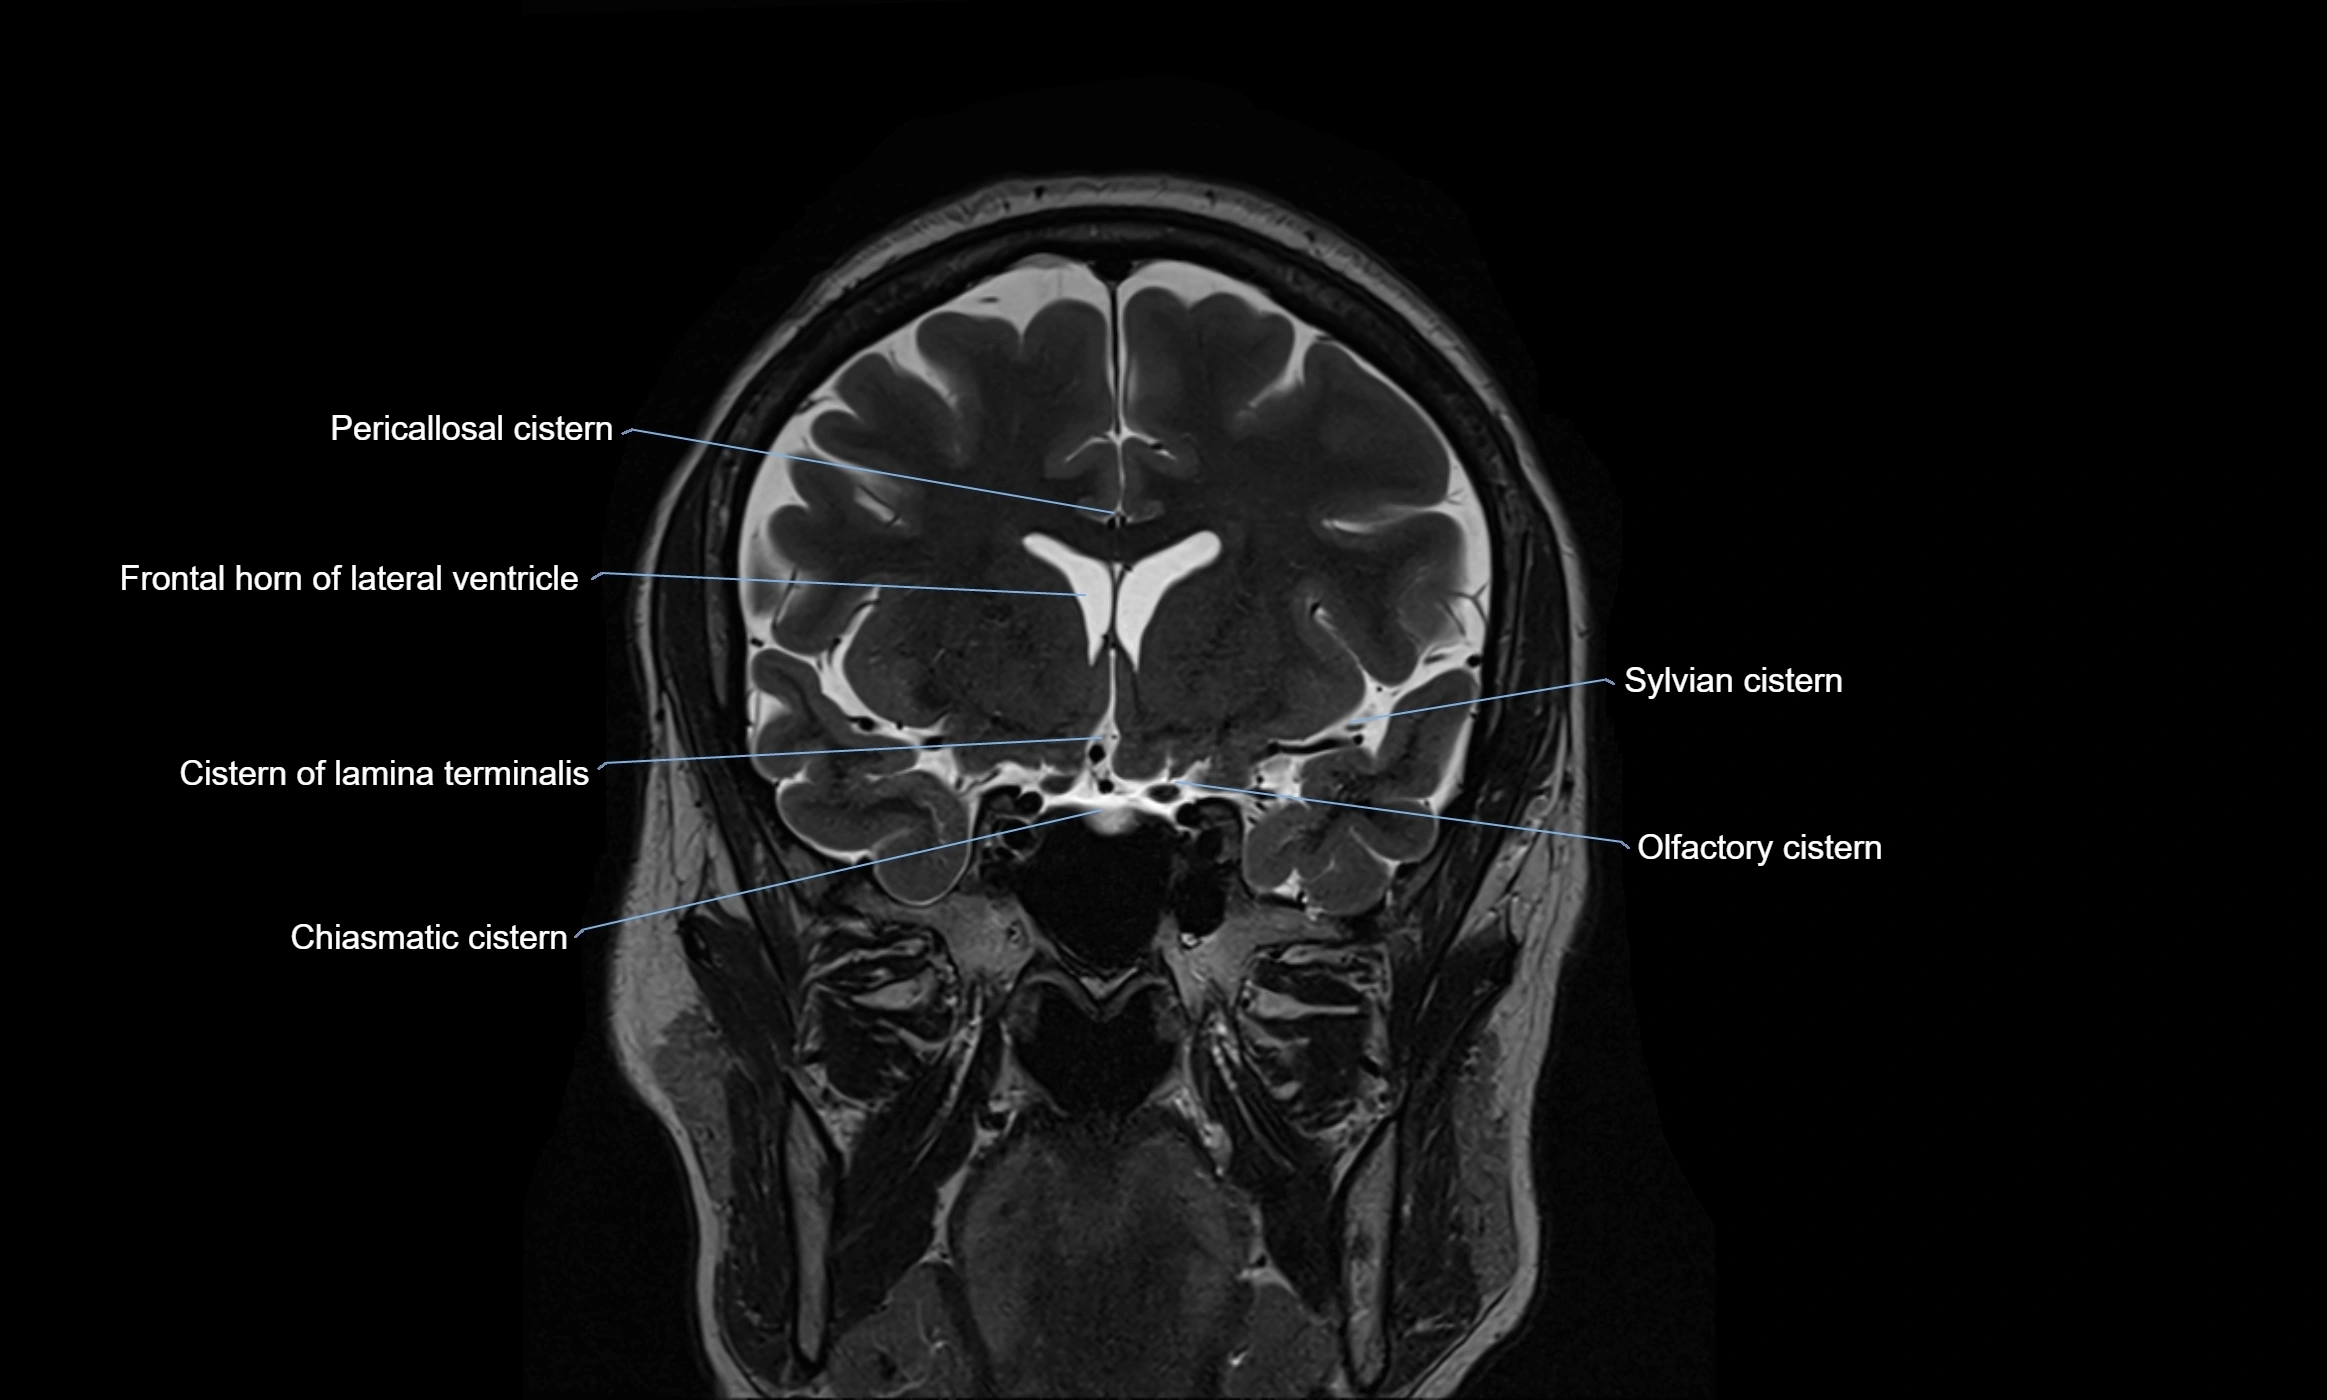

MRI images

image